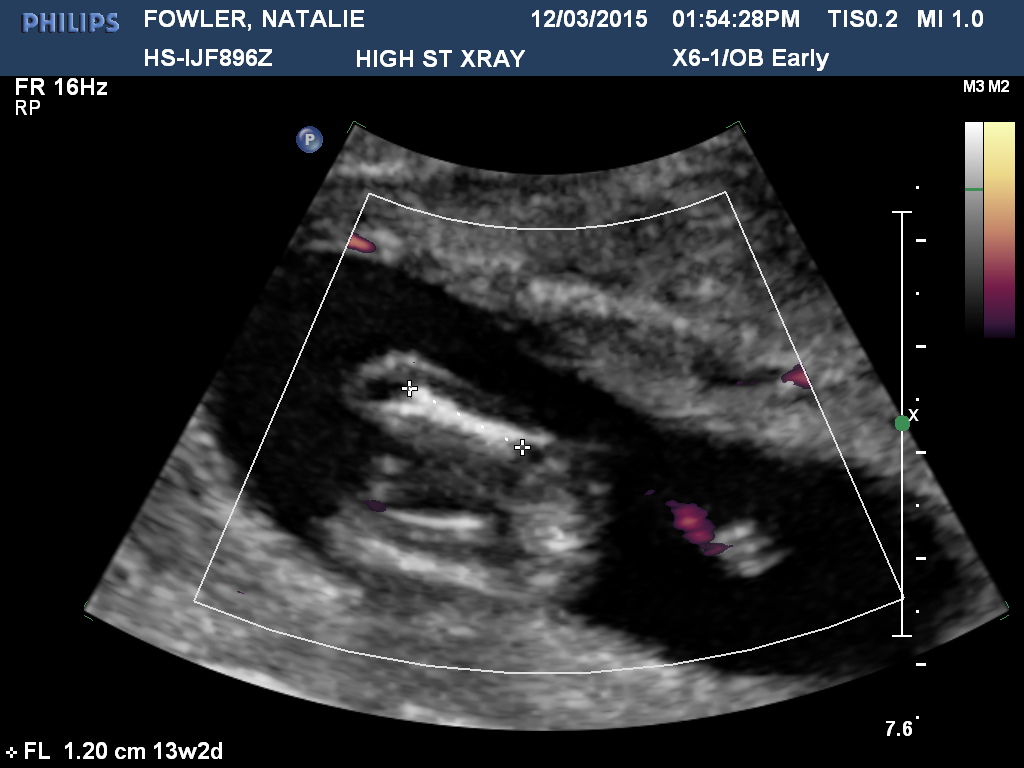

Thank you so much :) I'm not sure if this is the baby's nub but I thought I will post anyway :) Attachment 24232

I think the nub is a bit higher. Careful boy lean. Lots going on doen there

Had another scan done today and two techs said 80% girl :babyf: